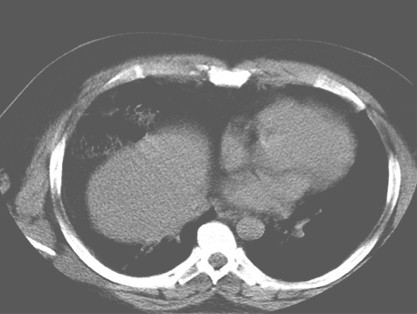

Se realiza Tomografía Axial Computarizada (TAC) multicorte observándose eventración diafragmática derecha situada hasta el límite del lóbulo medio con el lóbulo superior, integridad del diafragma, paso de órganos sólidos como el hígado y otros huecos como asas colónicas del ángulo hepático, desplazamiento de las estructuras del mediastino y corazón hacia el pulmón contralateral izquierdo. (Figuras 2 y 3).

Figura 2. TAC. Ventana mediastínica. Asas intestinales e hígado. Con desviación de estructuras del mediastino y corazón hacia el pulmón contralateral izquierdo.

Figura 3. TAC. Ventana pulmonar. Asas intestinales e hígado. Con desviación de estructuras del mediastino y corazón hacia el pulmón contralateral izquierdo.